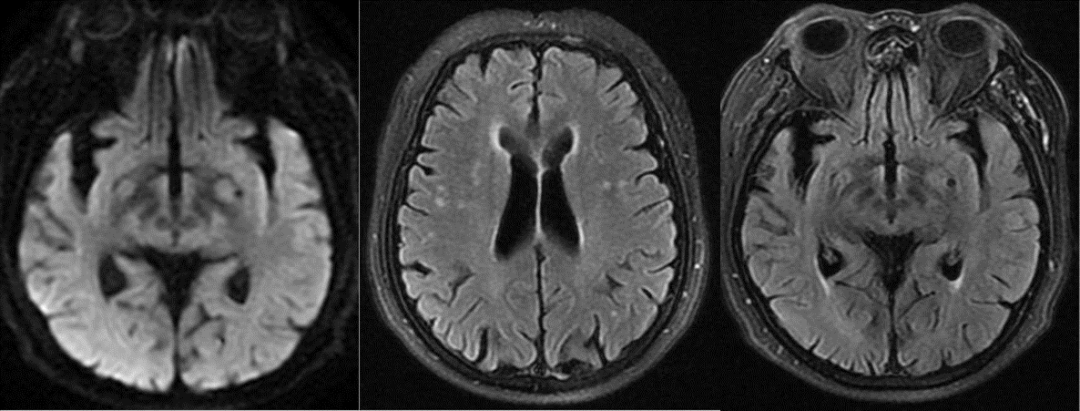

既往影像检查

导丝怎么扩【载药时代 球扩天下】NOVA DES®颅内药物洗脱支架在颈内动脉颅内段重度狭窄中的应用体会二例!_https://www.jmylbn.com_新闻资讯_第17张

DWI

导丝怎么扩【载药时代 球扩天下】NOVA DES®颅内药物洗脱支架在颈内动脉颅内段重度狭窄中的应用体会二例!_https://www.jmylbn.com_新闻资讯_第18张

MRA

头颅核磁:颅内多发缺血灶;DWI未见明显高信号;灌注可见右侧半球低灌注

导丝怎么扩【载药时代 球扩天下】NOVA DES®颅内药物洗脱支架在颈内动脉颅内段重度狭窄中的应用体会二例!_https://www.jmylbn.com_新闻资讯_第19张

头颅MRA:右侧椎动脉闭塞可能,双侧颈内动脉末端、左侧椎动脉V4段重度狭窄可能。